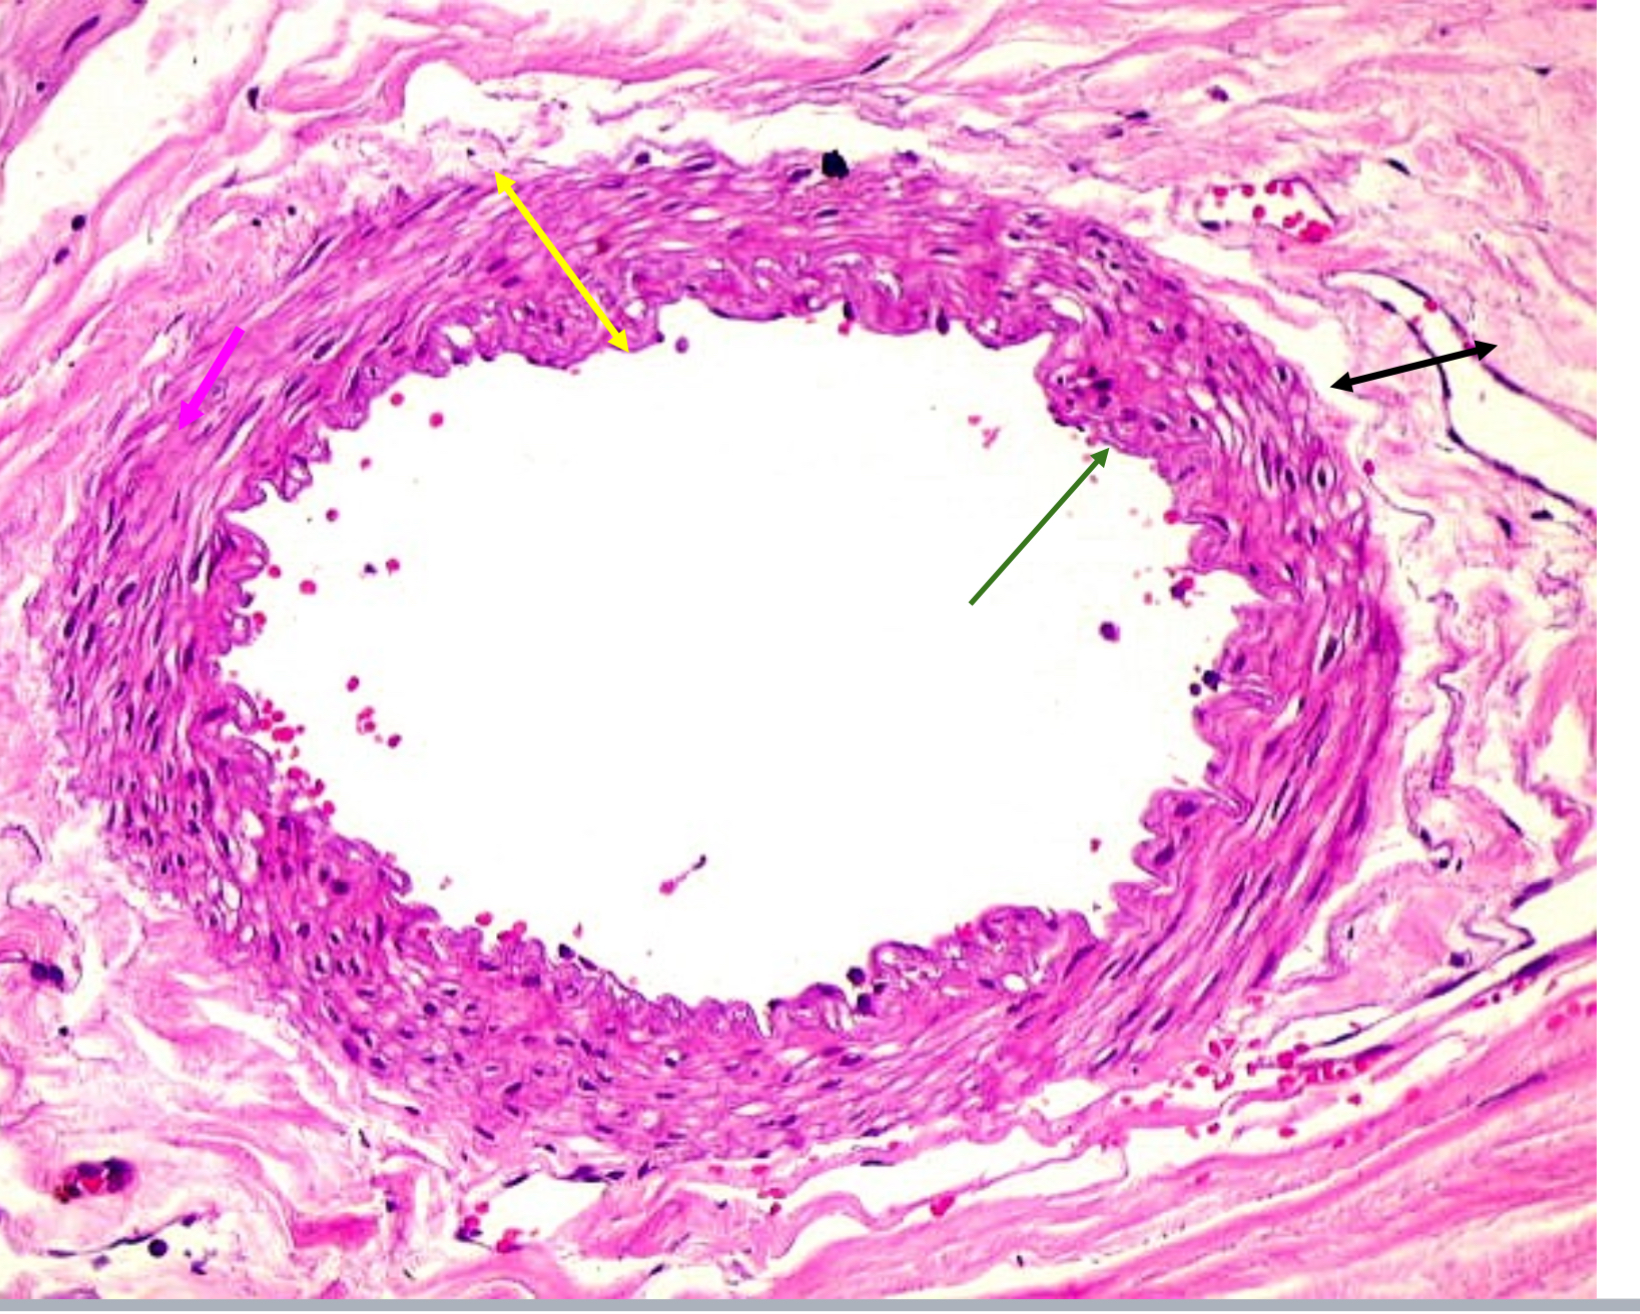

Tunica media

Name green arrow

Vasoconstriction and vasodilation

Function of tunica media

Tunica externa

Name the purple arrow

Anchor and bind vessel

Function of tunica externa

Artery

Artery or vein?

Vein

Artery or vein?

Tunica intima

Name the green arrow

Tunica media

Name the yellow

Tunica externa

Name the black